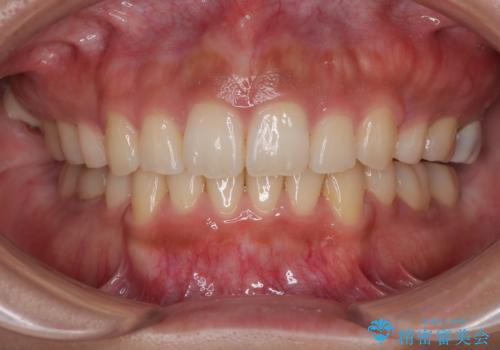

捻れて前に出ている前歯 ワイヤー装置での非抜歯矯正